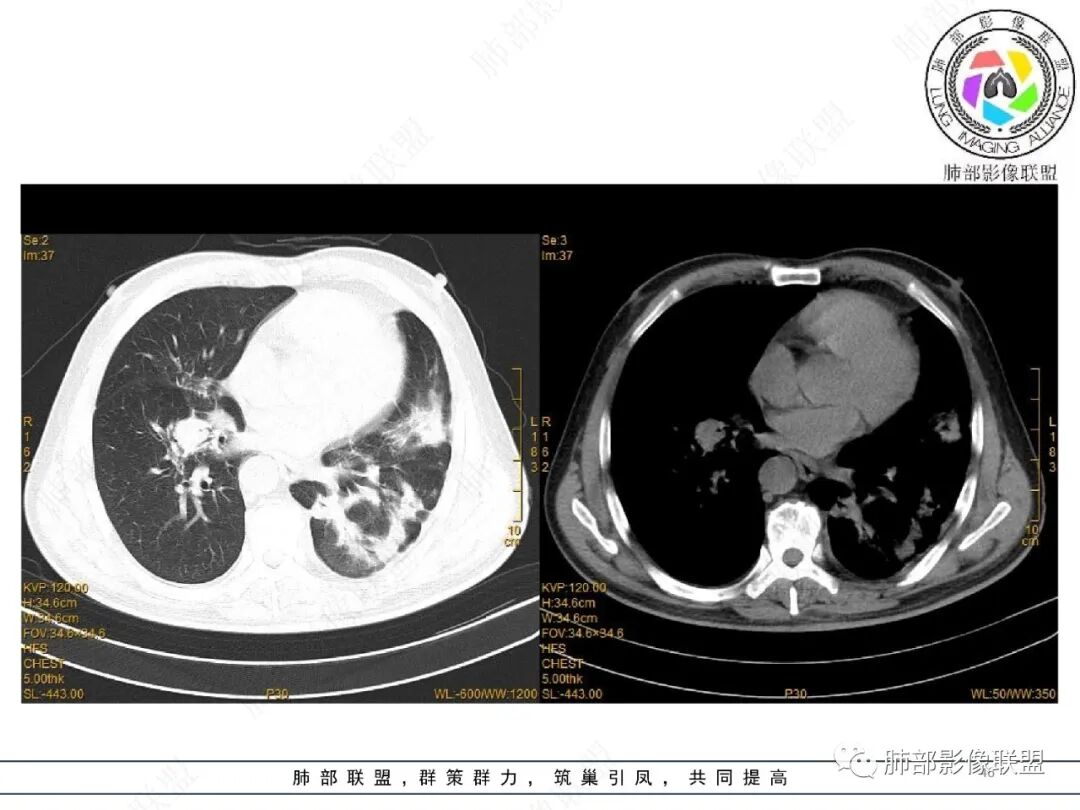

2022.2.17CT显示两肺中内带多发结节影、斑片影、条索影,部分病灶侧向融合与胸膜平行。部分病灶沿着支气管血管束分布、其内支气管稍扩张。部分病灶呈反晕征。大部分病灶边界显示清晰,部分病灶周围可见边界不清的GGO。2022.4.12CT显示两肺中内带多发结节影、条索状、条带状高密度影,边界收缩平直凹陷,大部分病灶沿着支气管血管束分布,亦有位于胸膜下侧向融合与胸膜平行的病灶。总体与第一次CT对比两肺病灶明显吸收。